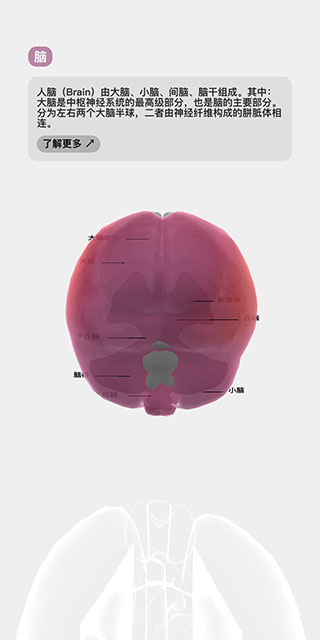

6、点击模型中的任意一个器官,它就会产生高亮效果,并且左上角的状态栏会切换显示为该器官的参数指标。

7、再次点击该器官,会显示它的具体说明信息,并在模型中标注出器官构成,点击下方的了解更多按钮,同样会进行浏览器跳转。